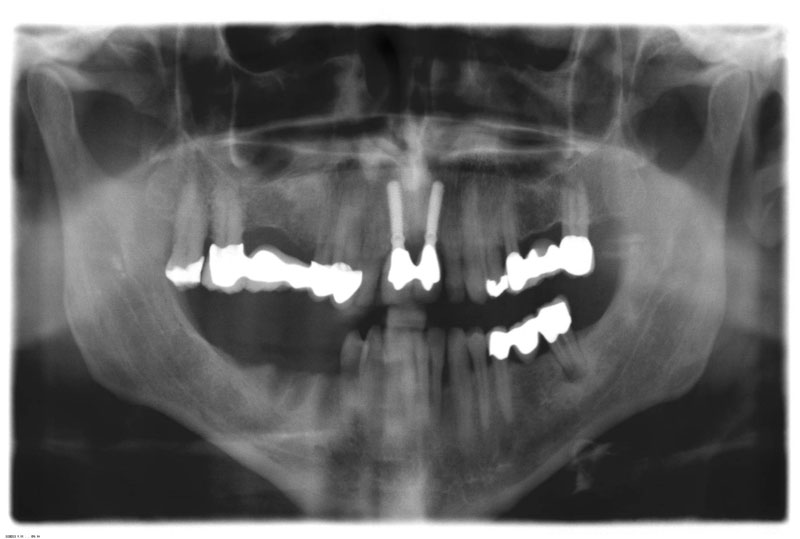

DVT mit 3D-Planung

Fehlen in der Front oder im Seitenzahnbereich mehrere Zähne, ist eine Brücke oder Prothese vollkommen unnötig. Die fehlenden Zähne können entweder einzeln durch eine entsprechende Anzahl von Implantaten oder durch implantatgetragene festsitzende Brücken ersetzt werden. Das Bild der Kronen zeigt die drei Verschraubungen deutlich, im Mund liegen diese verdeckt am Gaumen oder im Bereich der Zunge.